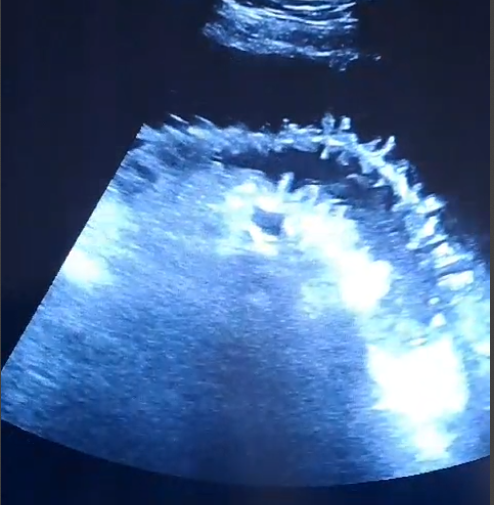

La paciente fue ingresada tras el diagnóstico de suboclusión intestinal. Se identificó mediante ecografía a pie de cama el signo de las «teclas de piano», característico de la obstrucción intestinal, lo cual orientó a un manejo conservador inicial. La paciente se mantuvo estable, sin signos de sufrimiento intestinal ni complicaciones mayores durante las primeras 24 horas. Se continuó con el manejo médico y se planificaron reevaluaciones frecuentes para monitorizar su evolución.

Este caso resalta la utilidad de la ecografía a pie de cama en el diagnóstico precoz de condiciones abdominales agudas como la suboclusión intestinal. En atención primaria, es fundamental reconocer signos ecográficos que permitan una evaluación rápida y precisa.